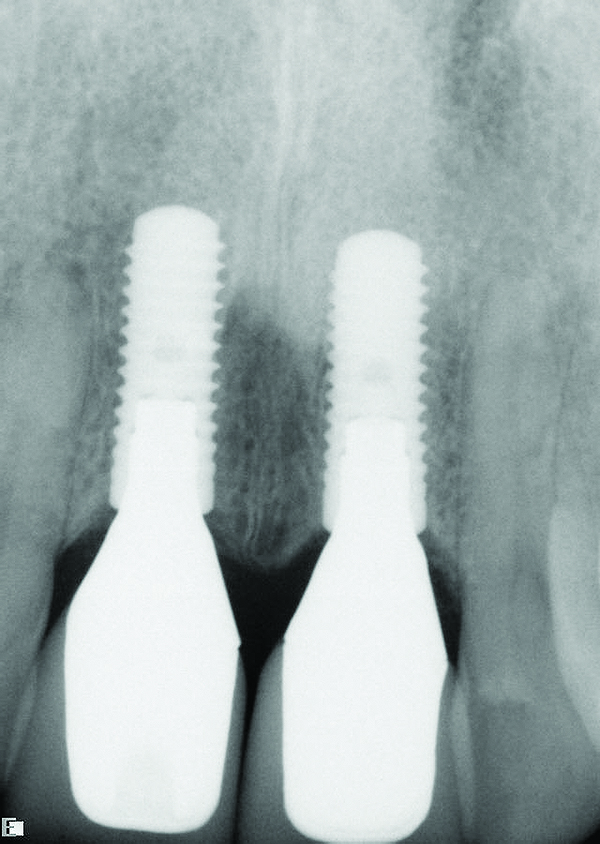

The DICOM (digital imaging and communications in medicine) images are then imported from the CBCT files into one of many commercially available implant-planning software programs. The surgeon and restorative dentist can then collaborate in choosing the precise position, angulation, and depth of implant placement, as well as the implant type, based upon a desired prosthetic outcome. Rosenfeld et al coined the term “collaborative accountability” to describe the pretreatment analysis and subsequent negotiated compromises between surgical and restorative colleagues on implant positioning and restorative design based upon anatomic limitations and the team’s willingness and ability to overcome them.3 Additionally, this pretreatment evaluation is invaluable in creating realistic patient expectations. Figure 1 through Figure 6 demonstrate a case showing 3-dimensional (3-D) presurgical planning, radiographic evidence of the plan’s execution, and 2-year follow-up. As a result of 3-D planning and subsequent guided implant surgery, the patient wound up with a pleasing, nature-like esthetic outcome (Figure 5).

Fig 1. Pretreatment plan for guided implant surgery to replace teeth Nos. 8 and 9.

Figure 1

Fig 3. Radiograph confirming that the implant placement matched the presurgical plan.

Figure 3

Fig 4. Radiograph taken on the day of delivery of the final implant-supported restorations, 3 months after implant placement.

Figure 4

Fig 6. Radiograph of crown Nos. 8 and 9, 2 years after implant placement.

Figure 6